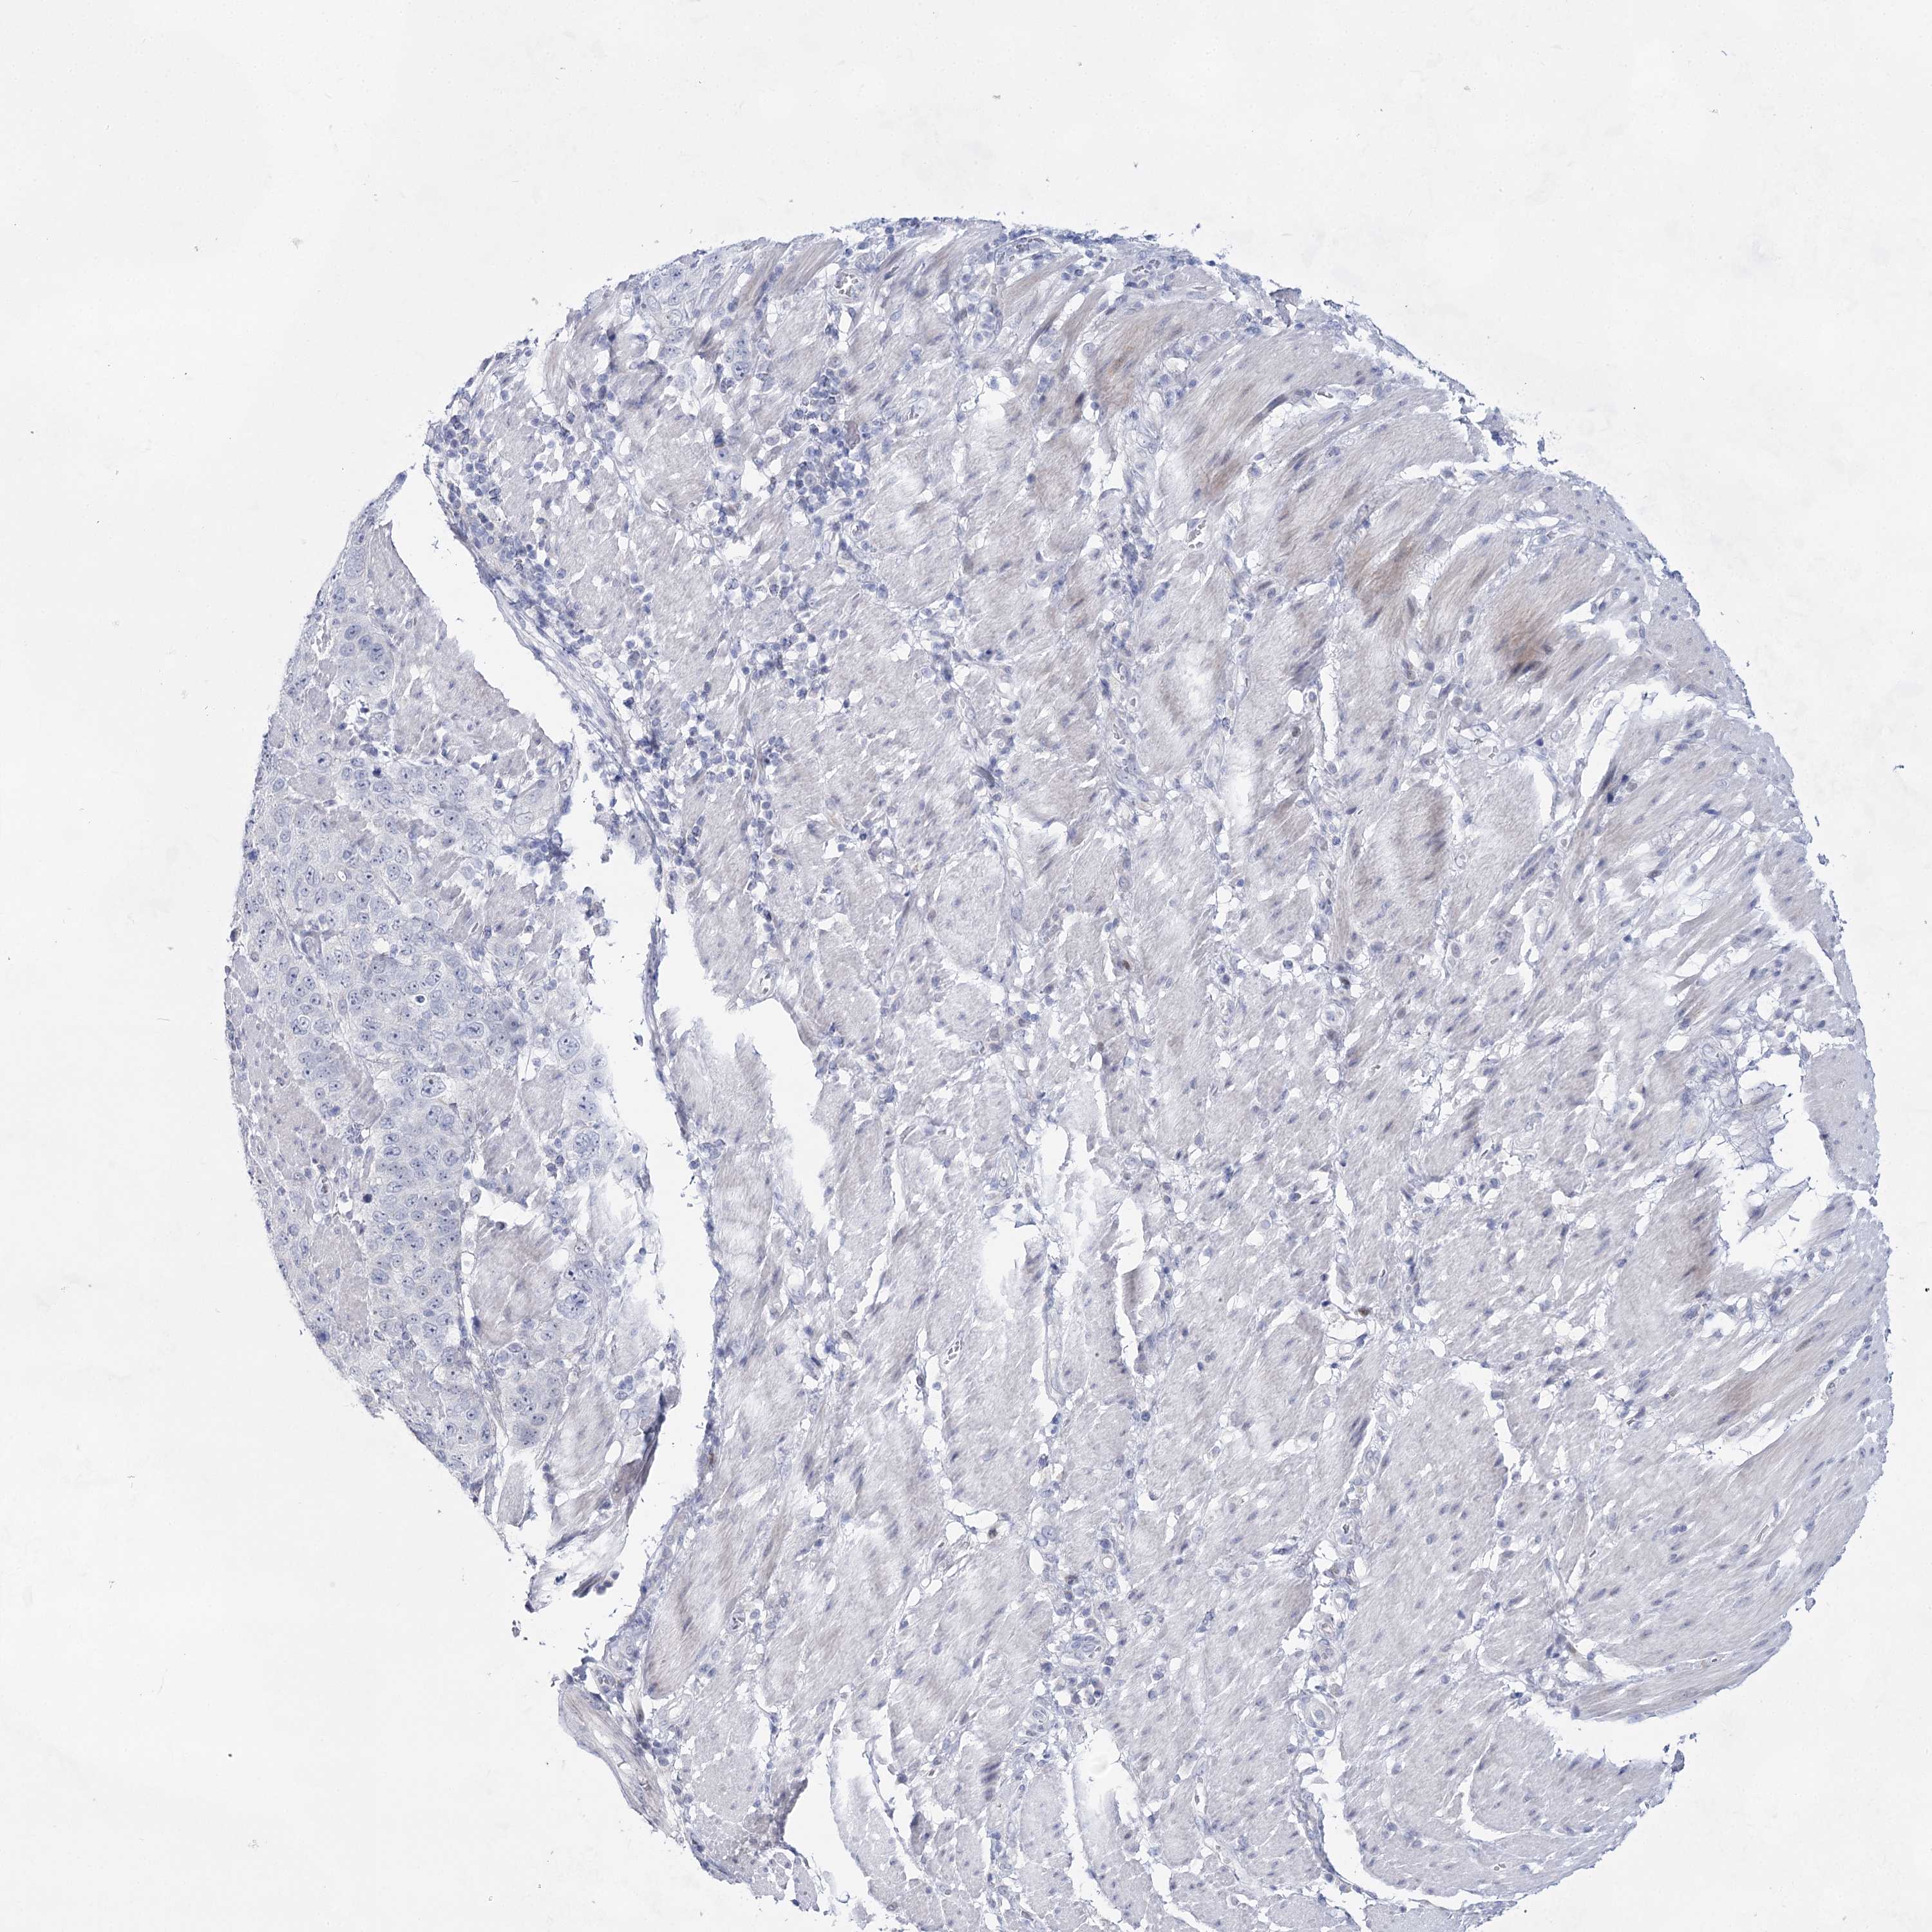

STOMACH CANCER - Protein expressioni

A mouse-over function shows sample information and annotation data. Click on an image to view it in a full screen mode. Samples can be filtered based on level of antibody staining by selecting one or several of the following categories: high, medium, low and not detected. The assay and annotation is described here.

Note that samples used for immunohistochemistry by the Human Protein Atlas do not correspond to samples in the TCGA dataset.

Antibody stainingi

Antibody staining in the annotated cell types in the current human tissue is reported as not detected, low, medium, or high, based on conventional immunohistochemistry profiling in selected tissues. This score is based on the combination of the staining intensity and fraction of stained cells.

Each image is clickable and will lead to virtual microscopy that enables deeper exploration of all samples and also displays staining intensity scores, fraction scores and subcellular localization as well as patient and tissue information for each sample.

Antibody HPA036752

Antibody HPA036753

Staining

High

Medium

Low

Not detected

Intensity

Strong

Moderate

Weak

Negative

Quantity

>75%

75%-25%

<25%

None

Location

Nuclear

Cytoplasmic/membranous

Cytoplasmic/membranous,nuclear

Adenocarcinoma, NOS